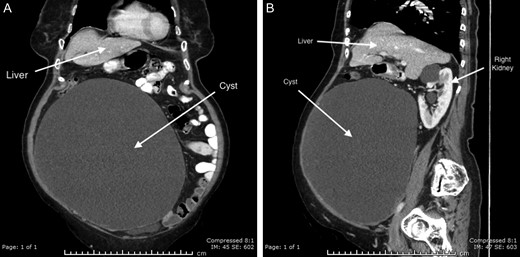

A contrast-enhanced CT scan of the abdomen and pelvis was performed, which revealed a large intra-peritoneal cyst measuring 21 × 25 × 26 cm3, containing simple fluid (Fig. 1). There were a few thin septations along the periphery with no appreciable nodular or soft tissue components within. The origin of the cyst was not able to be determined due to gross displacement of surrounding viscera. There was associated splaying of the bowel loops without resultant bowel obstruction. No pathologically enlarged abdominal, pelvic or inguinal lymph nodes were noted and there was no vascular compromise. On pelvic ultrasound, the majority of the lesion appeared simple cystic in nature. There was no obvious internal colour flow. Both ovaries were identified and appeared separate from the cyst.

CT abdomen with IV and oral contrast; (A) coronal and (B) sagittal.